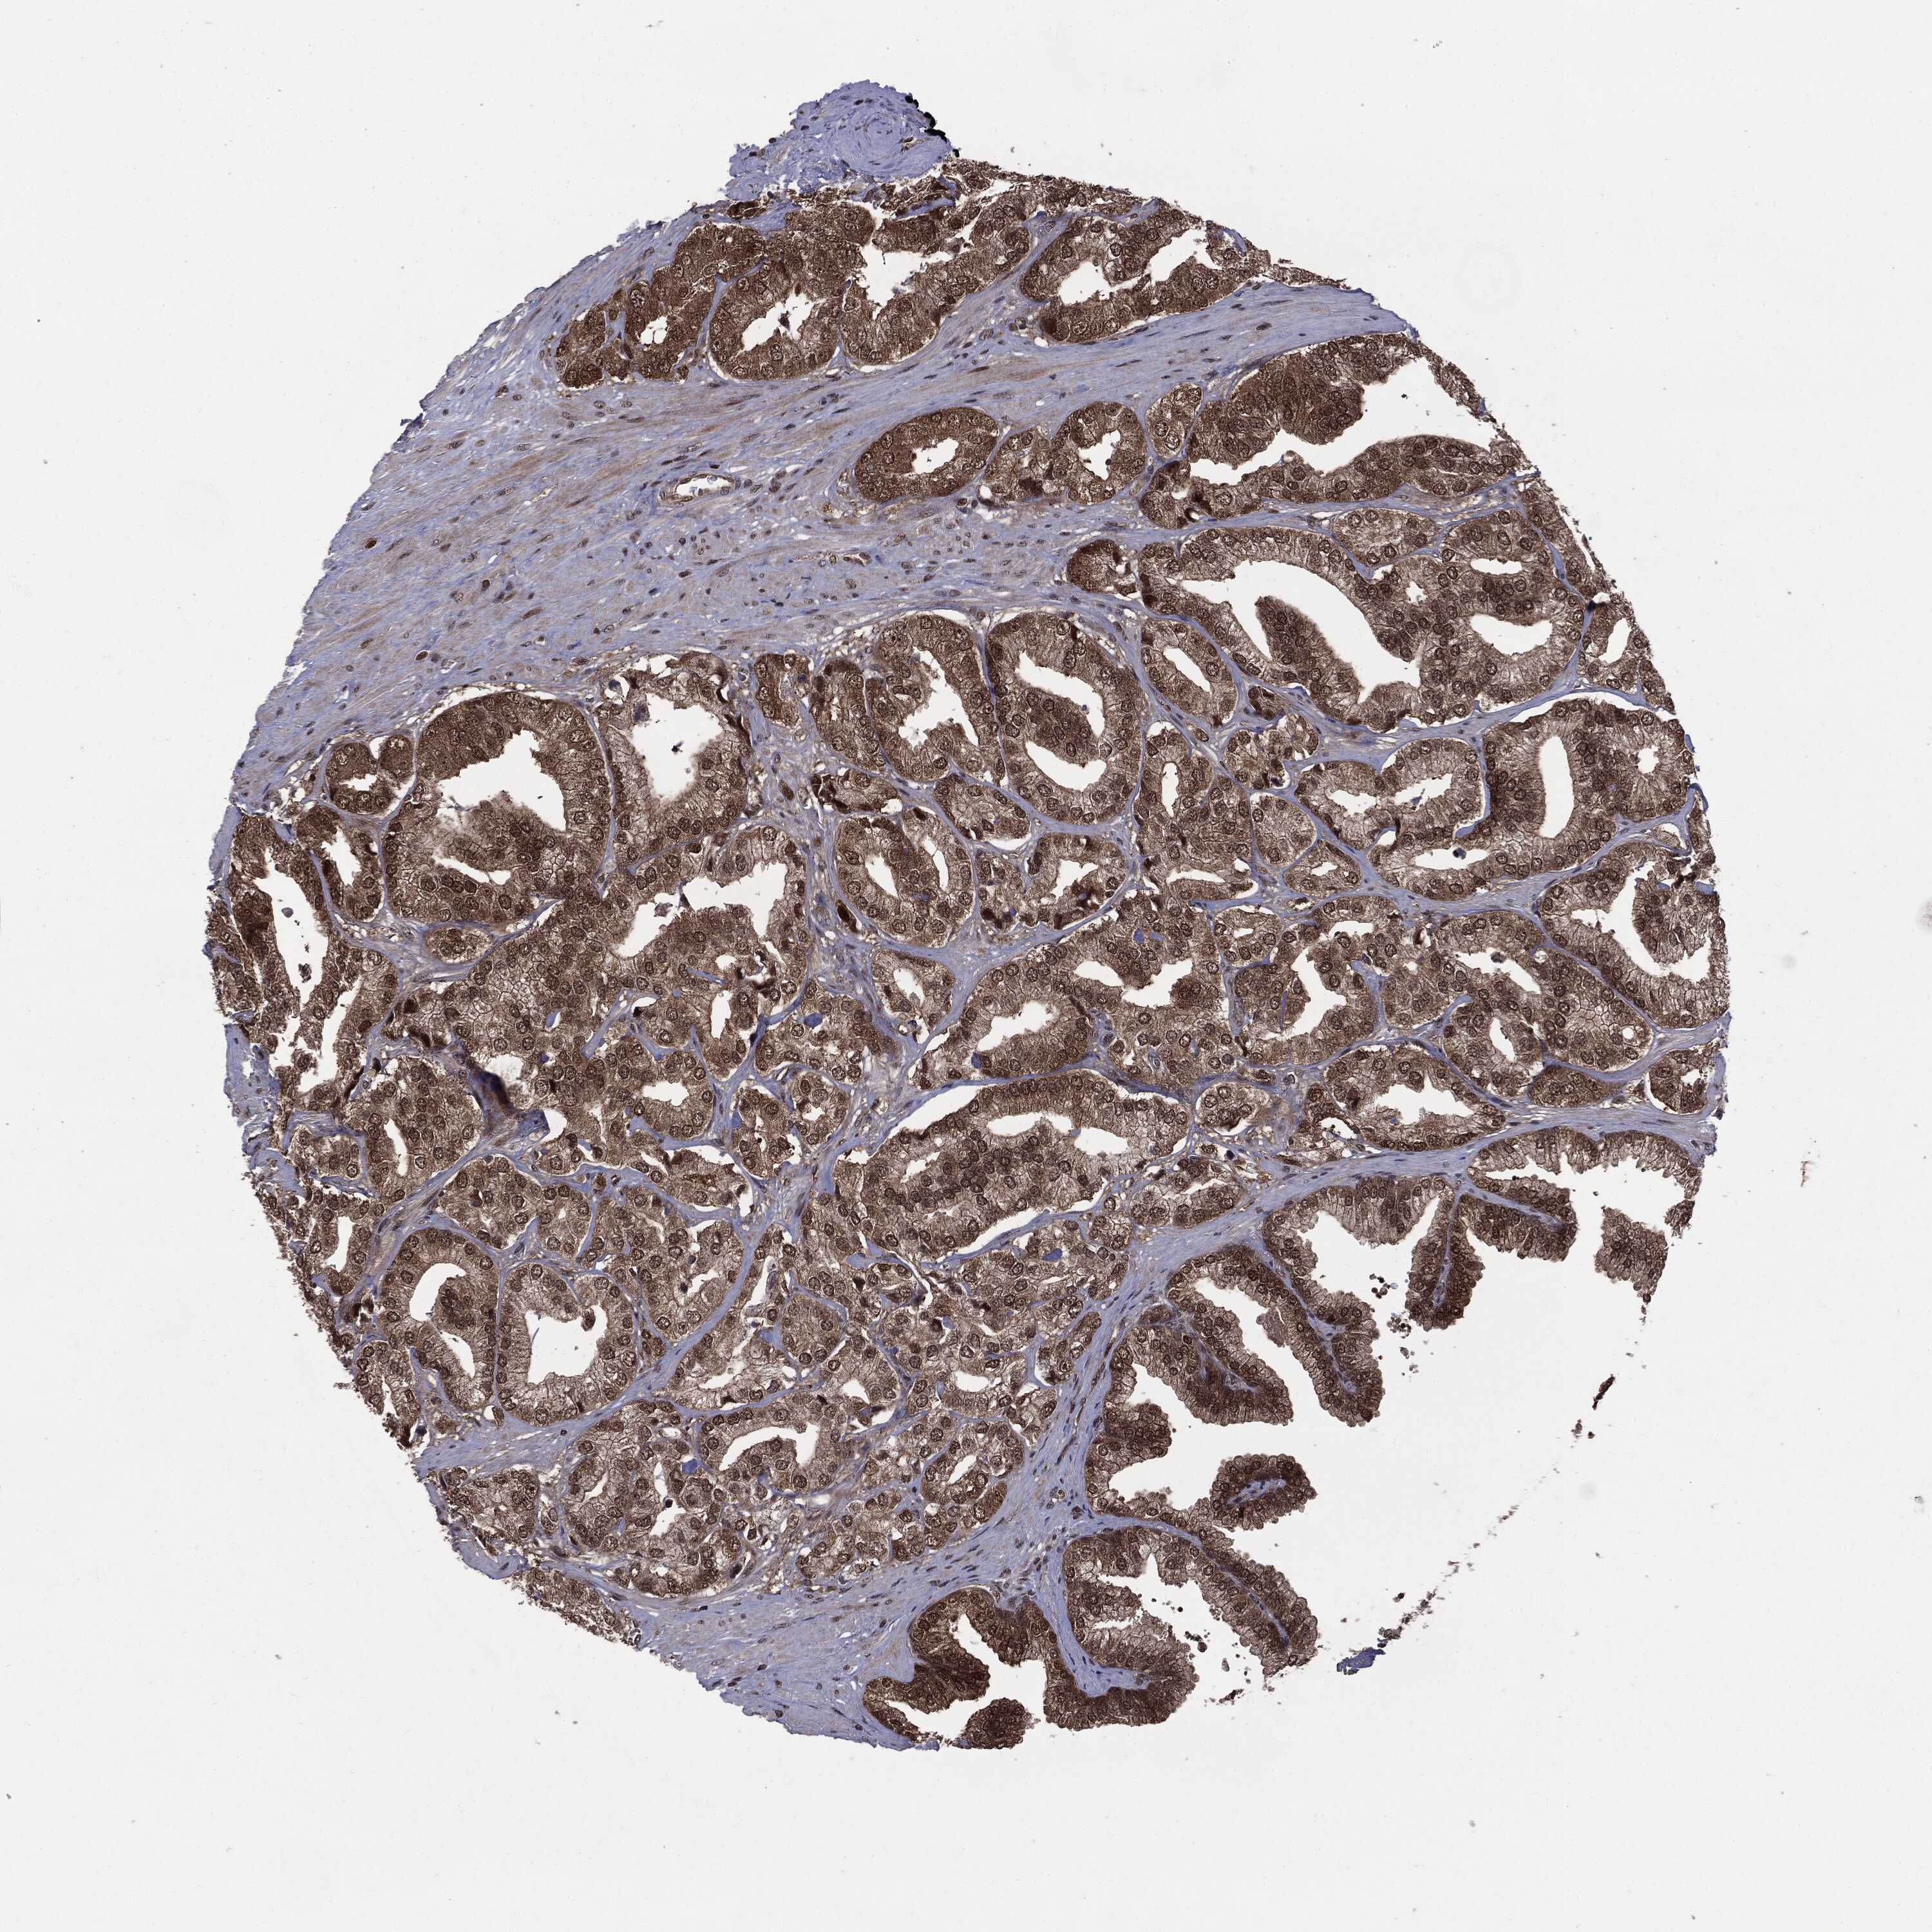

PROSTATE CANCER - Protein expressioni

A mouse-over function shows sample information and annotation data. Click on an image to view it in a full screen mode. Samples can be filtered based on level of antibody staining by selecting one or several of the following categories: high, medium, low and not detected. The assay and annotation is described here.

Note that samples used for immunohistochemistry by the Human Protein Atlas do not correspond to samples in the TCGA dataset.

Antibody stainingi

Antibody staining in the annotated cell types in the current human tissue is reported as not detected, low, medium, or high, based on conventional immunohistochemistry profiling in selected tissues. This score is based on the combination of the staining intensity and fraction of stained cells.

Each image is clickable and will lead to virtual microscopy that enables deeper exploration of all samples and also displays staining intensity scores, fraction scores and subcellular localization as well as patient and tissue information for each sample.

HPA005695

CAB022068

CAB035999

CAB080052

CAB080054

CAB080098

Adenocarcinoma, Low grade

Adenocarcinoma, High grade

Adenocarcinoma, NOS

Adenocarcinoma, Medium grade